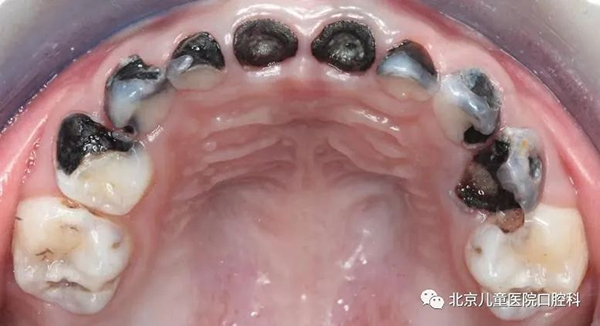

一、深龋引起的疼痛

孩子吃饭塞牙时疼,吃酸甜食物时疼,不吃的时候疼痛缓解。这种情况家长可以看看孩子塞牙的地方是不是有牙洞,如果有说明是龋齿来的疼痛。这种情况我们要加强口腔卫生,刷牙并使用牙线将嵌塞的食物剔除干净,同时控制冷热酸甜等刺激性大的食物。做到这些可以很大程度上缓解龋齿带来的不适,然后找时间来牙科门诊进行检查治疗。

深龋